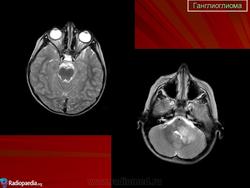

Продолжение.

Ганглиоглиома